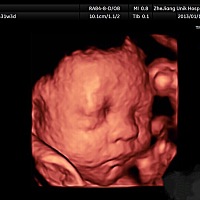

像吗,我们家的小男神